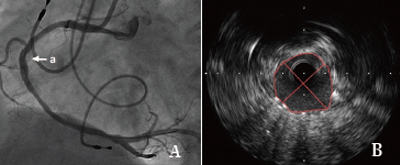

清华长庚医院3月23日电(心内科 薛亚军)我院心脏内科团队在王伟民教授指导下,成功为一名冠状动脉左主干加三支病变的急性心肌梗死的老人行冠脉介入手术治疗,术中应用血管内超声(IVUS)技术精准测量、定位病变,成功植入支架,标志我院心脏内科介入团队治疗复杂冠脉病变水平更上一层楼。

该患者于凌晨5点睡觉时突发胸痛,疼痛感向左侧肩部及后背放射,伴全身出汗以及恶心,并呕吐一次,胸口疼痛持续不缓解,由家里人送入我院急诊科,急诊科医师立即行心电图,结果提示心脏前壁、下壁、后壁心肌梗死,随后检验科回报心脏损伤标记物显著升高,急性广泛心肌梗死诊断明确,在张萍主任,缪国斌主任医师,薛亚军主治医师评估患者病情后,立即行冠状动脉造影显示冠状动脉左主干、前降支、左回旋支以及右回旋支均有广泛狭窄,情况复杂,随后在王伟民教授指导下使用血管内超声技术评估患者病变血管严重程度,并精确定位病变范围,支架大小,同时应用血管内超声技术评价支架植入后贴壁状况等,体现了我院倡导的“三精”医疗理念。术后患者平安返回病房,现病情恢复良好,胸痛症状未在发作。

血管内超声(intravenous ultrasound,IVUS) 是无创性的超声技术和有创性的导管技术相结合的一种新的诊断方法。运用该方法与传统的冠脉造影技术相结合可以准确评估血管的管壁形态及血管狭窄程度,在冠心病的介入性诊疗中有很高的指导价值。

传统冠脉造影只能显示管腔的情况,不能显示病变所在的管壁和粥样斑块,不能提供粥样斑块形态和性质的详细情况,有可能使医生低估冠脉狭窄的程度。这就使得依据冠脉造影评价冠脉粥样硬化和介入治疗疗效的准确度降低。血管内超声是利用导管将一高频微型超声探头导入血管腔内进行探测,再经电子成像系统来显示心血管组织结构和几何形态的微细解剖信息。由于超声探头直接置于血管腔内探测,因此,血管内超声不仅可准确测量管腔及粥样斑块或纤维斑块的大小,更重要的是它可提供粥样斑块的大体组织信息,在显示因介入治疗所致的复杂的病变形态时明显优于造影。